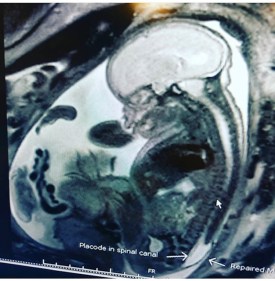

IMG_8653

My name is Erica and my daughter was diagnosed at 20 weeks. I am a nurse for an imaging center. My radiologists were the ones that had to break the news to me. My husband is also in healthcare as a respiratory therapist. Neither of us knew much of anything about Spina Bifida. But we began our research. We found the team at Children’s Hospital Colorado after being disqualified for fetal surgery from Texas Children’s and UCSF. We had to relocate from Idaho to Colorado leaving our 4 year-old son behind with family. Sloane and I had surgery at 24 weeks. We are currently 34 weeks and my c section is scheduled on October 29 at 37 weeks! Her Chiari has reversed, the patch on her back seems to be healing very well according to imaging, my fluid levels are staying good, and her ventricles remain normal in size. I can’t wait to meet my little warrior in a few short weeks.

IMG_8651

UPDATE:  This is little Sloane.  She was born on 10/20/18 and everyone is doing well!